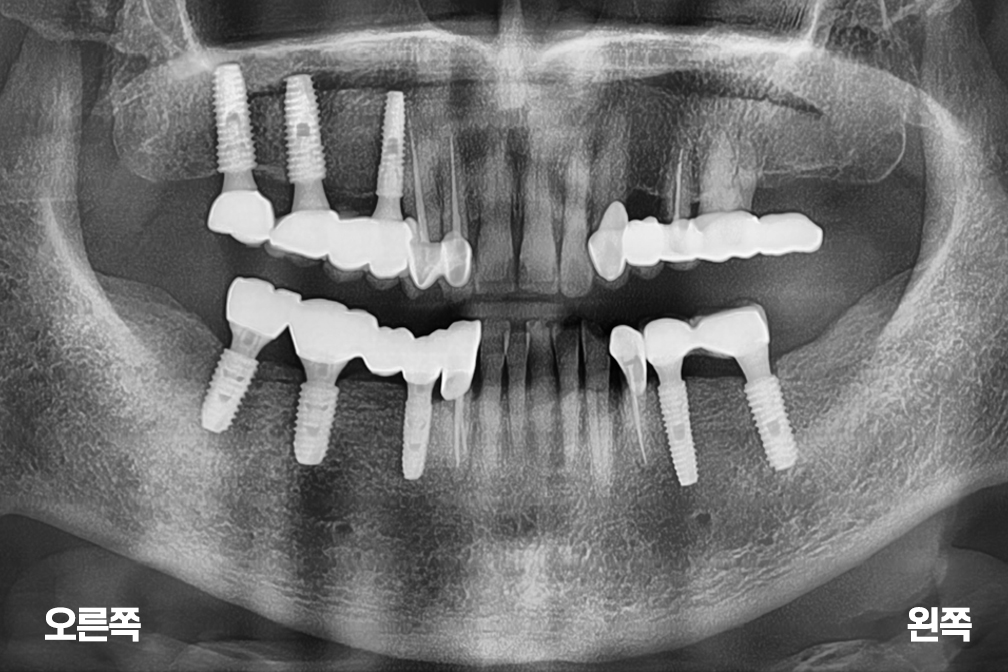

임플란트 오른쪽 아래 기존 보철물 제거 후 브릿지 + 어금니 임플란트 수술

어금니 임플란트

Before 2025년 5월 30일

After 2026년 3월 24일-